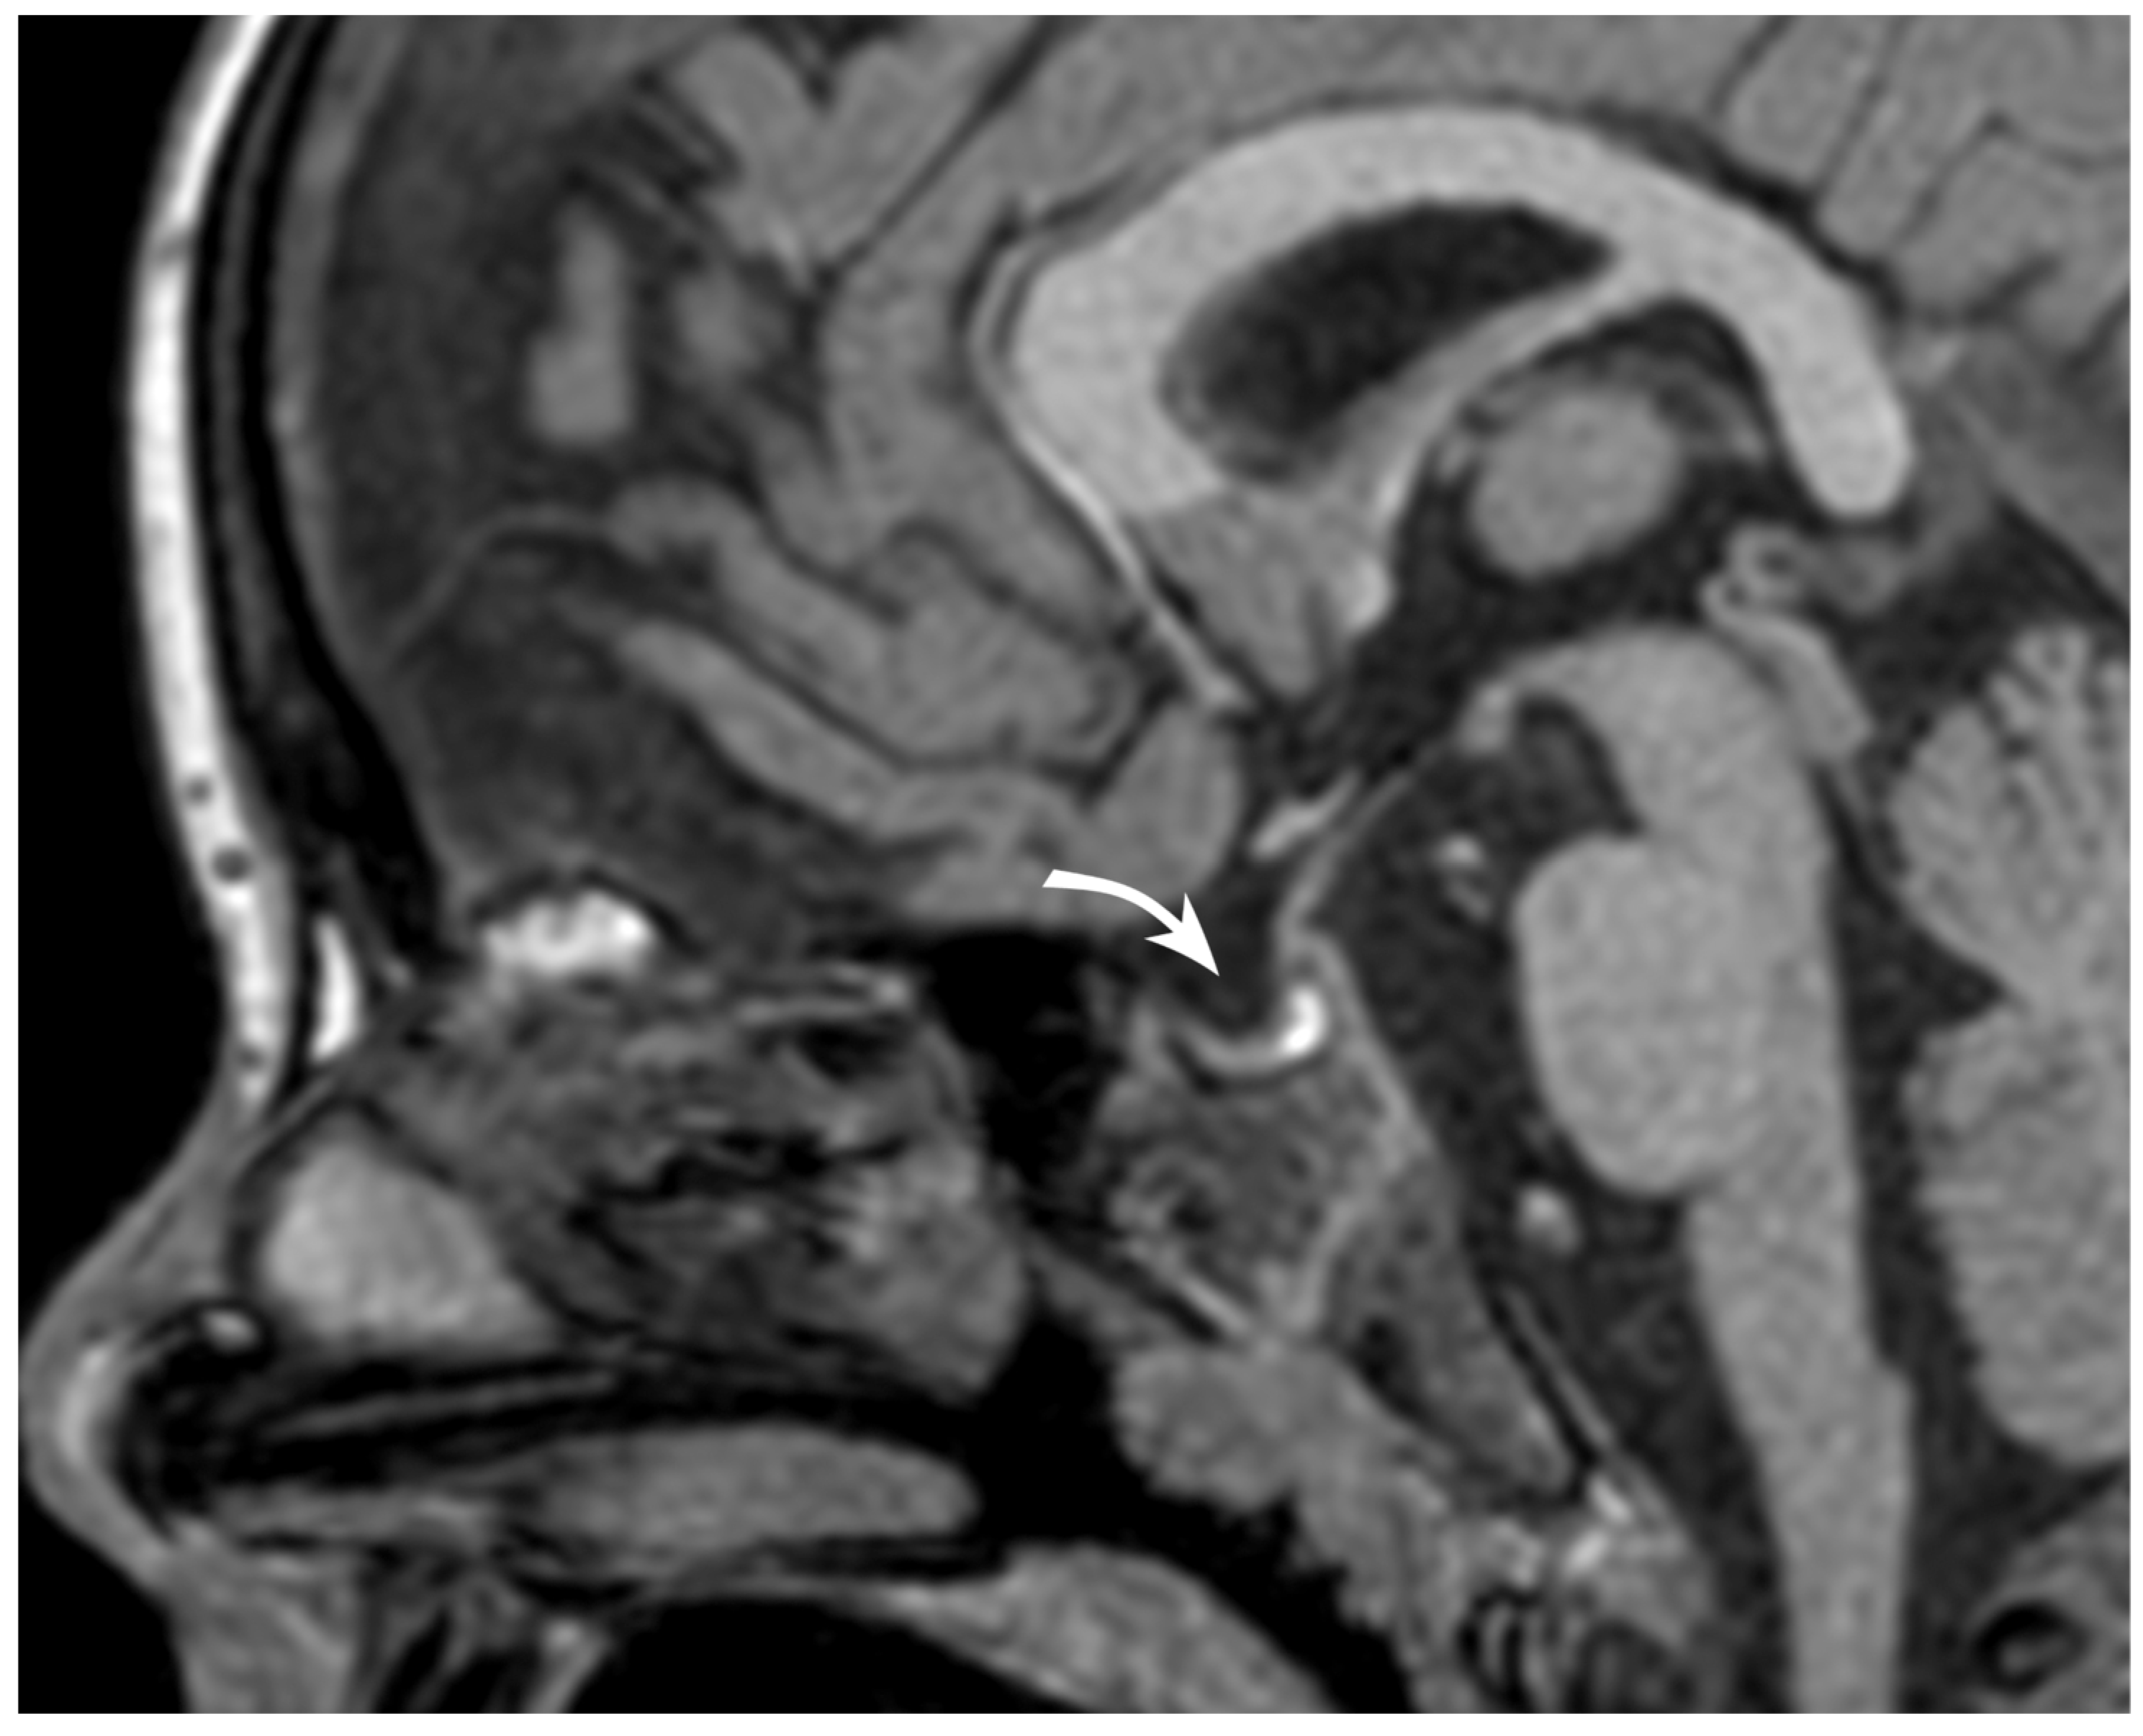

3.1. Case Report